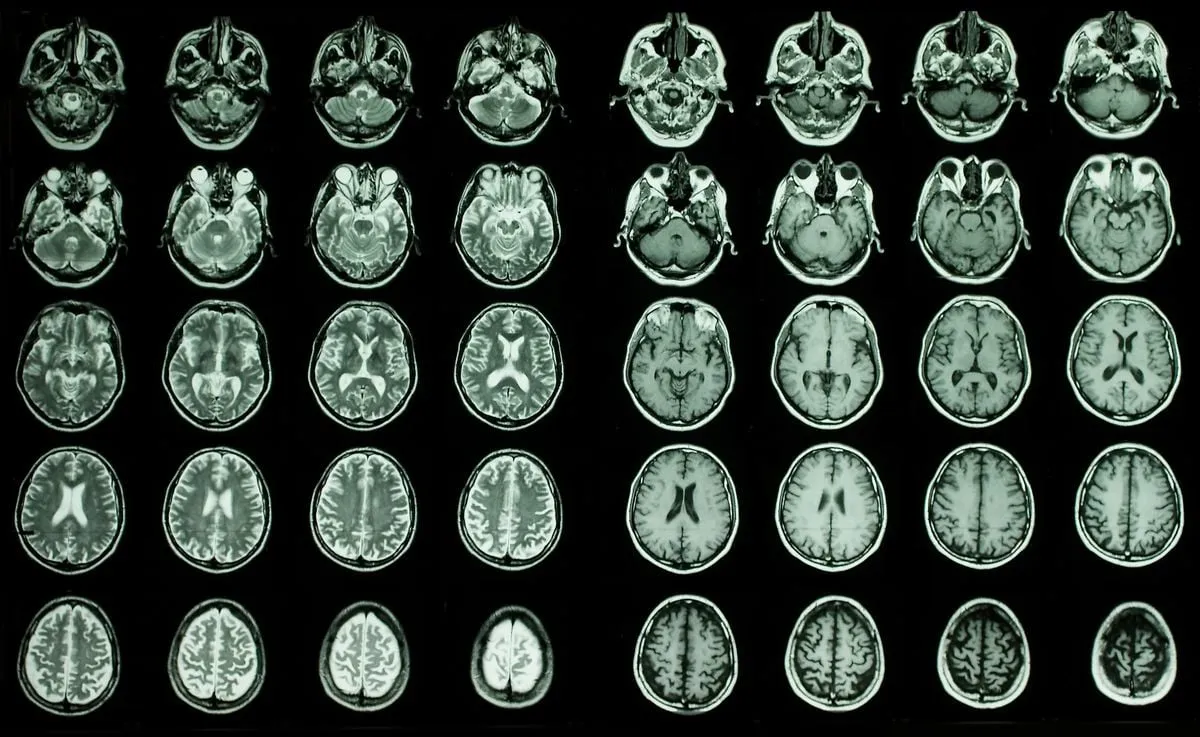

Linking brain aging, a recent study highlights the identification of 13 blood proteins associated with cognitive decline potential. This discovery presents a promising avenue for future diagnostics and targeted therapies.